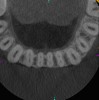

Surveying pulpal anatomy before initiating treatment is another area in which CBCT can benefit a trained operator. Understanding the internal anatomy of the root canal system can help in treatment planning a nonsurgical case, as well as a microsurgical case, to avoid procedural mishaps. CBCT can also facilitate the conservation of tooth and root structure.For instance, knowing whether a maxillary molar has a second mesiobuccal (MB) canal can help the practitioner avoid troughing or removing precious dentin when there is no MB2 canal. In addition, more accurately locating the MB2 canal when it is visible on CBCT also assists in conserving tooth structure. The same holds true for a possible lingual canal or additional canal(s) in a mandibular incisor (Figure 9) or bicuspid.

Fig 9. 3D CBCT image of mandibular incisors with two canals.

Figure 9